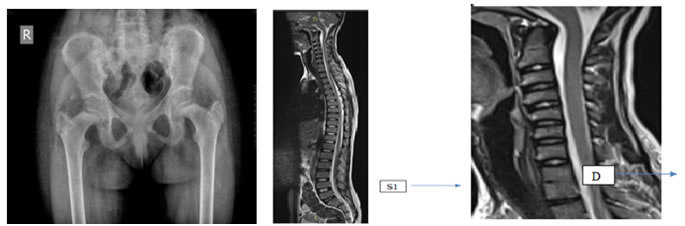

Figure 1: Figure 2: Figure 3:

Figure 1: X-ray pelvis: Irregular subarticular surfaces of bilateral sacroiliac joints. Decreased hip joint spaces bilaterally with coxavara deformity

Figure 2: MRI whole spine: (T2WI)=Lumbarization of S1 and S2 vertebrae noted.

Figure 3: MRI Saggital T2WI: Partial Fusion of D1 and D2 vertebrae.

Figure 4: MRI Cervical Spine Saggital T2WI sequence: Subtle clivus odontoid angulation with angulation of caudal portion of medulla oblongata and proximal portion of spinal cord.